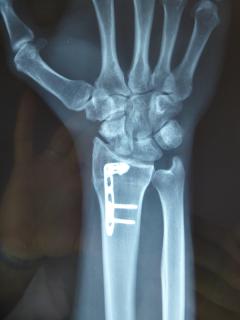

Μετεγχειρητικά 1

Η αντιμετώπιση της ψευδάρθρωσης του σκαφοειδούς είναι πάντοτε χειρουργική. Με ραχιαία ή παλαμιαία προσπέλαση αποκαθίσταται ο άξονας του σκαφοειδούς και σταθεροποιείται το σκαφοειδές με ειδική βίδα ή βελόνες, με παράλληλη τοποθέτηση οστικών μοσχευμάτων. Μπορεί επιπλέον να γίνει και οστεοτομία κλειστής σφήνας του περιφερικού άκρου της κερκίδος. Στις περιπτώσεις άσηπτης νέκρωσης το μόσχευμα πρέπει να είναι αγγειούμενο – για να προσδώσει αιμάτωση στο νεκρωμένο κεντρικό τμήμα – και λαμβάνεται με μικροχειρουργικές τεχνικές από το περιφερικό τμήμα της κερκίδος ή από άλλα τμήματα του σώματος